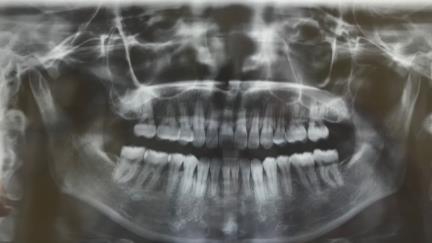

6號磨牙缺失,智齒牽引前的牙片

而有智齒可以幫忙,正畸醫生一般會考慮選擇牽引智齒來代替磨牙發揮功能,比如上圖所示,6號牙壞掉,可以通過智齒牽引把智齒拉到7號牙的位置,而把7號牙拉到6號牙的位置。如此一來,一石二鳥,既節省了種牙的時間、費用,也保留了自己的健康智齒。

6號牙缺失,牽引智齒替代7號牙的牙片